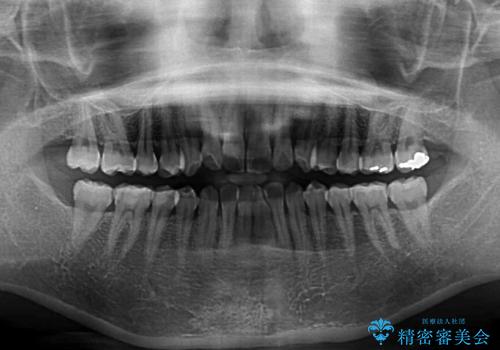

- ワイヤーではない矯正治療があると聞いたとのことで来院された患者様です。

長年前歯のデコボコを気にしていたもののワイヤー矯正に抵抗があり躊躇していたそうですが、インビザラインなら治療してみたいとのことで相談にいらっしゃいました。

インビザライン適用の歯列であったため、歯と歯の間を削るIPRを用いて改善することとしました。

下顎前歯の叢生が顕著な場合、歯列改善後に歯と歯と歯肉の間にブラックトライアングルという隙間ができてしまいます。

軽減することはできますが、完全に解決することは矯正治療のみでは不可能なため、リスクとして事前に周知しておく必要があります。